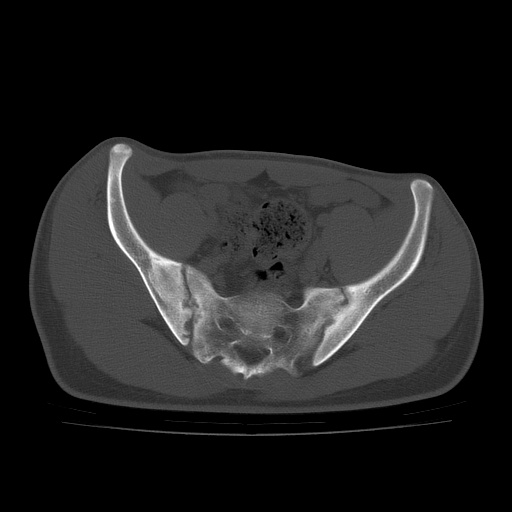

患者男性,18岁 腰腿痛1年  骶髂关节改变本人考虑强直性脊柱炎。

两侧骶髂关节骨质破坏,关节面毛糙,符合强直性脊柱炎骶髂关节改变。

符合强直性脊柱炎,虫蚀样骨质破坏。

两侧骶髂关节骨质破坏,关节面呈锯齿样改变关节间隙变窄,考虑强真性脊柱炎

双侧骶髂关节关节间隙变窄,边缘毛糙,关节面硬化,可见囊变!符合强直变现!

两侧骶髂关节骨质破坏以髂骨为主,间隙变窄,强直性脊柱炎